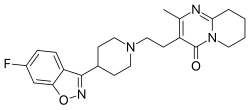

Neuroleptika

Die von den klassischen Neuroleptika abweichenden klinischen Eigenschaften zahlreicher atypischer Neuroleptika werden mit einer über eine Hemmung von Dopaminrezeptoren hinausgehenden zusätzlichen Hemmung von Serotoninrezeptoren des Subtyps 5-HT2A erklärt (Dopamin-Serotonin-Hypothese). Atypische Neuroleptika wie beispielsweise Clozapin, Olanzapin und Risperidon haben eine im Wesentlichen verbesserte Wirkung auf die Negativsymptome der Schizophrenie sowie eine reduzierte Häufigkeit extrapyramidal-motorischer Nebenwirkungen und Spätdyskinesien. Das Verhältnis aus der Affinität eines Neuroleptikums zu 5-HT2A-Rezeptoren zu seiner Affinität zu D2-Rezeptoren, auch Meltzer-Index genannt, dient in diesem Zusammenhang der Vorhersage atypisch-neuroleptischer Eigenschaften.[87]